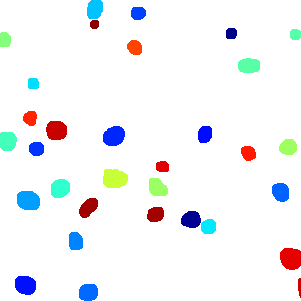

The task of nuclei segmentation can be roughly divided into two stages: the first stage is extracting the foreground(nuclei), the second stage is segmenting the connected foreground area into separated nuclei and finding out the boundary of each nucleus. Our method intends to merge these two steps by extracting the nuclei and their edges at the same time. That is the reason why it is named ”nuclei-boundary(NB) model”. As shown in Fig.3, the output of the NB model has three channels, each has the same height and width with the input image. Its values represent the probabilities of each pixel being , or class, respectively. The manual annotation for our segmentation problem is the boundary of each nucleus. A pixel belonging to the class means that it is on or inside an annotated boundary and within 2 pixel from the boundary. Pixels of the class are those that are inside annotated boundary but are not pixels. Correspondingly, the output can be regarded as an RGB image and the estimated maps of the , and are represented by red, green and blue, respectively, as shown in Fig.3. To generate the ternary mask for training, we apply a morphology operator to each nucleus to obtain the pixels, and then subtract pixels from the nucleus to get pixels.

II-C5 Post-processing

From Fig.6, we can see that the raw prediction results already show clear nucleus areas and boundaries. Due to this reliable prediction results, we no longer need the complex region growing algorithms [22, 17] and splitting algorithms [27] to extract the final segmented areas. These methods usually strongly rely on manual parameter tuning to get good performance and is computationally demanding. Instead, we use a parameter-free postprocessing procedure that runs in a negligibly short time. Since our NB model detects both and classes, all we need is the class map. Then the class map is transformed to a binary map using a constant threshold . In this way, each connected component in the binary image indicates the area of one nucleus. At the end, in order to recover the shape, we can simply apply the dilation operation to each connected component.

Figure 6 shows how our method segments the nuclei step by step. The color variety is well controlled by the color normalization procedure. The prediction result shows clear nuclear areas and nucleus boundaries. In the final segmentation result and ground truth image, each nucleus is represented by a different color.